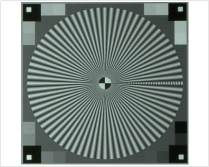

| 空間響應頻率 | 西門子星圖 |  | YY/T1587-2018YY/T1603-2018 | |